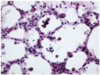

Histological appearance of what circulatory disorder

Edema